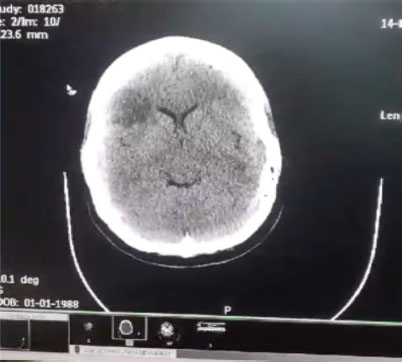

Tomografía de cráneo: con área hipodensa, circunscrita, de bordes simétricos, en territorio de M1- M2 derecha (Figura 4). |

Al cuarto día de su ingreso hospitalario, la paciente presentó un cuadro caracterizado por paraparesia inferior de aparición insidiosa, además de la sintomatología por lo que fue ingresada inicialmente. Esto nos planteó la posibilidad de una lesión neurológica focalizada en la médula espinal o estructuras supramedulares; ante la evolución del cuadro y la aparición del déficit motor, se realizó una tomografía axial computarizada de cráneo sin contraste, cuyos hallazgos (Figura 4) mostraron un área de hipodensidad en los territorios M1 y M2 correspondientes a la arteria cerebral media derecha, lo que objetivó la presencia de una lesión isquémica en dicha distribución, clinicamente concordante con el compromiso motor evidenciado.

Figura 4. Tomografía axial de cráneo sin contraste con área de hipodensidad en los territorios M1 – M2 de la arteria cerebral media derecha

Fuente: Tomografía institucional registrada durante la hospitalización. Uso aprobado por la paciente y familiares conforme a normas éticas de confidencialidad.

En el contexto de las manifestaciones neurológicas y tras la identificación de una lesión hipodensa en los territorios M1-M2 de la arteria cerebral derecha en la tomografía axial de cráneo sin contraste; se solicitó interconsulta al servicio de Neurología para valoración especializada. Luego de la evaluación clínica y revisión de los estudios por imagen, el equipo neurológico consideró que los hallazgos eran compatibles con una enfermedad vasculocerebral de tipo isquémico en fase aguda versus subaguda, por lo que se instauró tratamiento dirigido a la misma, incluyendo medidas de soporte, control de factores de riesgo vascular y prevención secundaria.